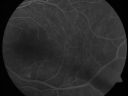

Sturge-Weber Encephalotigeminal Angiomatosis - Facial Hemangioma and Asymptomatic Ipsilateral Diffuse Choroidal Hemangioma752 views61-year-old man with Sturge-Weber syndrome with a hemangioma on the left side of his face.

VISUAL ACUITY: Vision OD is 20/50, PH 20/30; OS 20/80, PH 20/30. IOP: OD 16, OS 19.